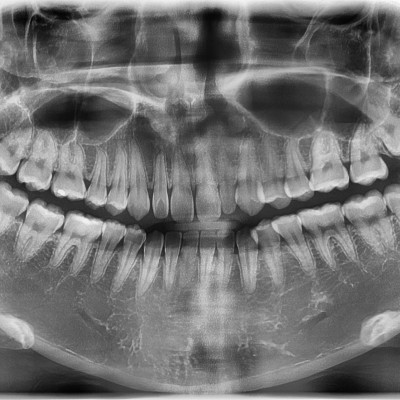

#18,28,38,48 사랑니 발치 #18,28,38,48 사랑니 발치 구강 외과 전문의가 당일 발치했습니다. --------------------..

작성자 이턱이 작성일 02-04 조회 1